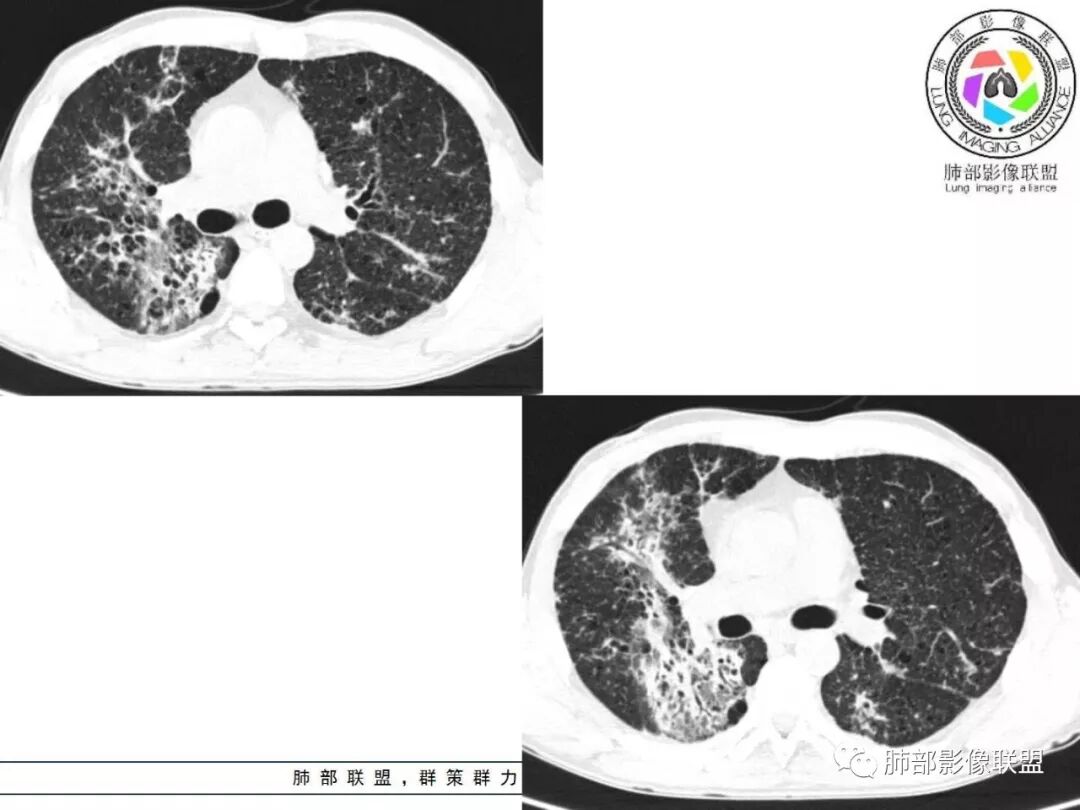

胸部CT:两肺弥漫病灶,磨玻璃影,少许实变,部分累及胸膜,磨玻璃区可见囊?少许胸腔积液,两肺可见结节,支气管血管束增粗,小叶间隔增厚,支气管走形有扭曲扩张,可见纤维化。气肿、大泡。考虑:感染性病变,PCP?查下HIV,CD4,G等。鉴别结核、结缔组织病肺浸润。

患者中年男性,发热1月,体温38℃-39℃,峰值40℃,无畏寒、寒战,伴黄痰,CRP升高明显,降钙素原稍升高,血沉、血糖正常。胸部CT:两肺弥漫病变,磨玻璃影+点片渗出,部分累及胸膜,磨玻璃区边界清楚,少许胸腔积液,两肺支气管血管束增粗,小叶间隔增厚,部分支气管走形有扭曲扩张,可见肺气肿、右肺尖肺大泡及部分纤维化改变。综合考虑:感染性病变。结核或PCP可能性大,鉴别风湿免疫、结缔组织疾病肺浸润和腺癌等恶性病变。

双肺弥漫性病变,多发磨玻璃密度及小叶间隔增厚,大部分沿支气管血管束分布,伴支气管轻度扩张,以午后及晚上发热为主,考虑感染性病变,间质性结核可能大,另双肺多发肺气囊,LIP待排

中老年男性,双肺弥漫性病变,呈网状、斑片及大片状,实变影及磨玻璃影相间,部分病灶区支气管扩张,并见多发小囊状或蜂窝状透亮影,中央间质增厚,气管前单发小淋巴结。考虑淋巴细胞增生性病变?粘膜相关性淋巴瘤(MALT)或淋巴细胞间质性肺炎(LIP)?鉴别机化性肺炎(OP)及结核(TB)。

两肺弥漫病灶,中央间质分布为主,部分位于胸膜及叶间裂旁,磨玻璃影,斑片影,部分实性结节,肺气囊,支气管血管束增粗,小叶间隔增厚,叶间裂不均匀增厚。考虑:间质性肺病,LIP,鉴别OP

双肺肺气肿背景,双肺弥漫分布磨玻璃及实变密度,病灶沿血管支气管束及胸膜下分布为主,部分病灶以平直收缩为主,局部支气管稍扩张,管壁增厚,小叶间隔增厚,结合临床病史,考虑炎性病灶,感染伴病灶机化?结核?NTM?

中老年男性,发热1月余,双肺弥漫性病变,多发网格、结节、斑片状实变影及磨玻璃影,胸膜下及中轴间质都受累,支气管血管束增粗、变形,支气管扩张,叶间裂及小叶间隔增厚,整体间质性改变明显,考虑结核?OP、LIP?进一步除外PCP、肿瘤、结节病等。

2. 肺气肿背景(小叶中心性肺气肿);双肺多发病灶整体沿血管支气管束及胸膜下分布,以上叶及下叶背段分布为主,有实变及GGO,边界清楚,有树芽,小叶间隔及中央间质增厚,叶间裂见到多发结节,部分支气管不规则牵拉扩张,提示病灶纤维化明显,结合临床病史,考虑病灶为间质性感染,肺门及纵隔内有钙化淋巴结,小叶间隔结节,考虑淋巴道增值性疾病可能,综合常规要怀疑间质性肺结核。